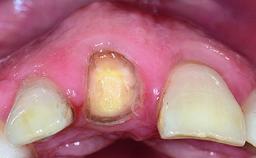

Replacement of a Missing Upper Left Central Incisor: Late Placement of an RC Bone Level Implant, CAD/CAM Zirconia Abutment

Eduardo R Lorenzana, Jason R Gillespie

A healthy 37-year-old female patient was referred for a consultation on the replacement of missing tooth 21 with an implant-supported restoration. She stated that several years previously the tooth had been traumatically avulsed following a motor vehicle accident. The tooth was replaced with a three-unit fixed partial denture (FPD) immediately afterwards. Over time, she became disillusioned with the FPD and looked for a different option, including orthodontic therapy. She presented still in her orthodontic appliances, with the pontic sectioned free from the FPD but attached to the archwire. Her orthodontist felt that orthodontic treatment had been successfully completed, but nevertheless referred her before removing the appliances in case adjustments were necessary.

Bone Volume Deficient horizontally, allowing simultaneous augumentation

Soft Tissue Contour and Volume Slightly compromised